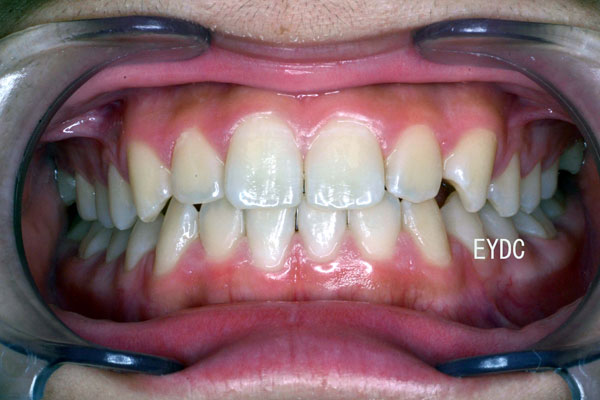

11才7ヶ月。これで完成です。もう装置は付けなくてかまいません。歯並び育成期間は6年でした。熱意をもって通院してくれたお母さんとご本人のがんばりでこんなにきれいになりました。愛くるしくてカワイイお顔をお見せできないのがとっても残念です。この後は経過観察に入ります。